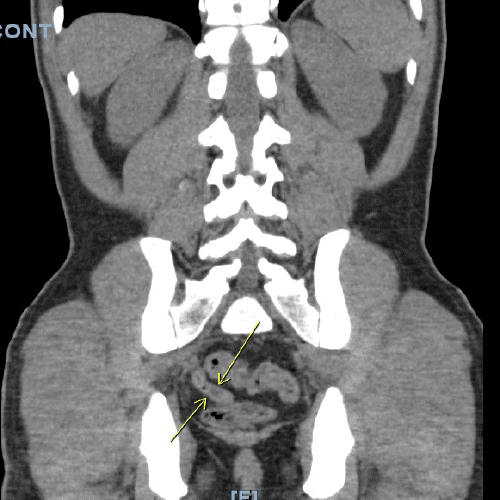

On physical examination, his vitals were within normal limits. He was very thin and had diffuse palpable lymphadenopathy in the cervical and inguinal regions and a large mobile left cheek mass. His abdominal exam was benign, with no anterior abdominal pain but rather bilateral flank pain. The patient's leukocytosis was 13,000 k/cm2, with the remainder of his labs within normal limits; the cluster of differentiation 4 (CD4) count was 2670, and the viral load was 1,391,823. HTLV-I/HTLV-II antibodies were positive. A CT of the abdomen and pelvis with oral and intravenous (IV) contrast was obtained, showing acute tip appendicitis (Figure 1) and extensive bulky gastrohepatic, periportal, peripancreatic, retroperitoneal/para-aortic, bilateral iliac chain, and bilateral inguinal lymphadenopathy (LAD) (Figure 2) with mild splenomegaly suggestive of lymphoma. A CT maxillofacial scan to evaluate his cheek mass also demonstrated extensive bulky cervical lymphadenopathy as well as an enlarged mandibular mass (Figure 3). Of note, the patient had a CT scan performed one year prior that showed an appendix with the same diameter but no local inflammation (Figure 4).

Figure 2. CT Scan: Abdominal and Inguinal Lymphadenopathy. Published with Permission

Figure 3. CT Scan: Cervical Lymphadenopathy. Published with Permission